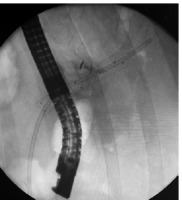

Figure 2

A 5 fr APC probe (ERBE, FiAPC 1500A) used to ablate the scar tissue obstructing the self-expandable metal stent. APC settings: Forced APC 70 Watt, 1 l/min